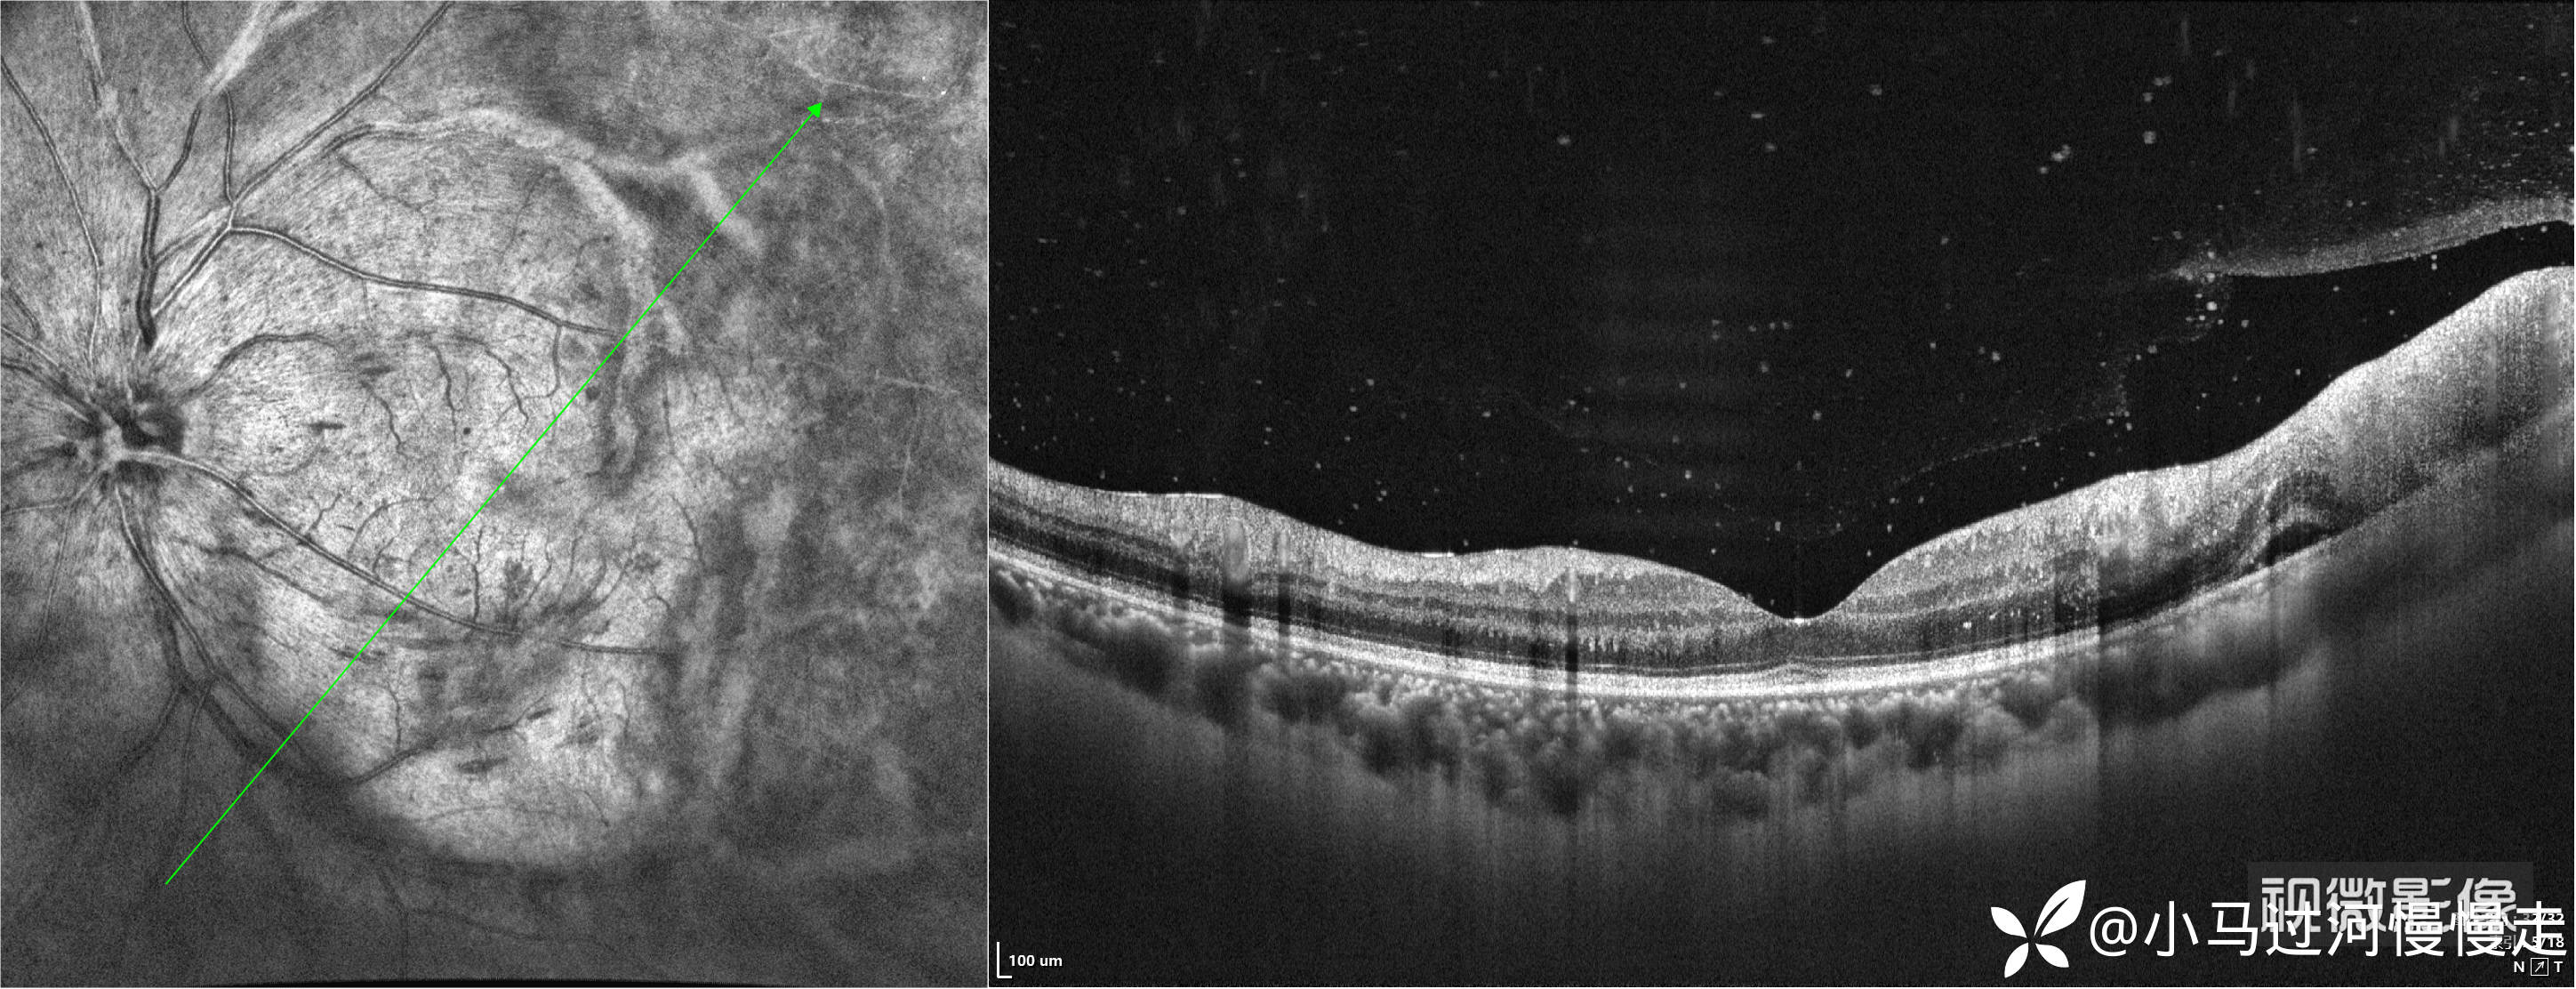

当时正在试用视微SSOCT,记录了左眼颞侧病变的影像。

依据患者AIDS病史,典型的眼部表现初步诊断了巨细胞病毒性视网膜炎(CMVR),后患者外院就诊确诊了CMVR,没有回来复查,这是我唯一见过的HIV合并CMVR的病例。